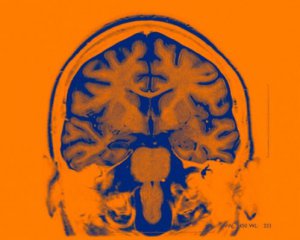

Американские ученые встроили в человеческий мозг имплант для контроля настроения.

Имплант опробовали на 6-ти добровольцах. Авторы идеи предлагают использовать мозговые имплантаты для лечения разнообразных нервных нарушений, например, депрессии.

Мозг зависимо от настроения человека делает разнообразные электромагнитные колебания.

Ученые убеждены, что новые открытия помогут в лечении больных, страдающих депрессией, а кроме этого разными психологическими нарушениями. В дальнейшем ученые полагаются сделать "библиотеку" мозговых паттернов для лечения самых разнообразных нарушений.